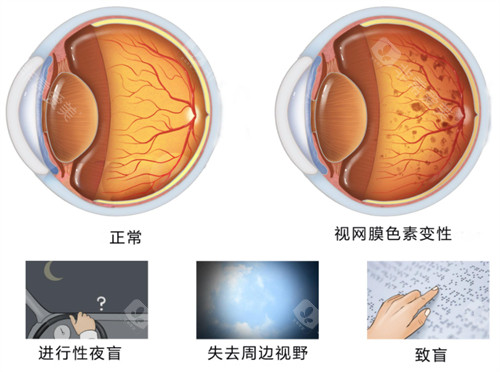

糖尿病视网膜病变,也被称为糖尿病性视网膜病变或糖网病。它是由于糖尿病导致视网膜微血管受损,进而影响视力。

随着病情的发展,患者可能出现视力下降、视物模糊、眼前黑影等症状,重度时甚至会导致失明,给患者的生活和工作带来极大不便。